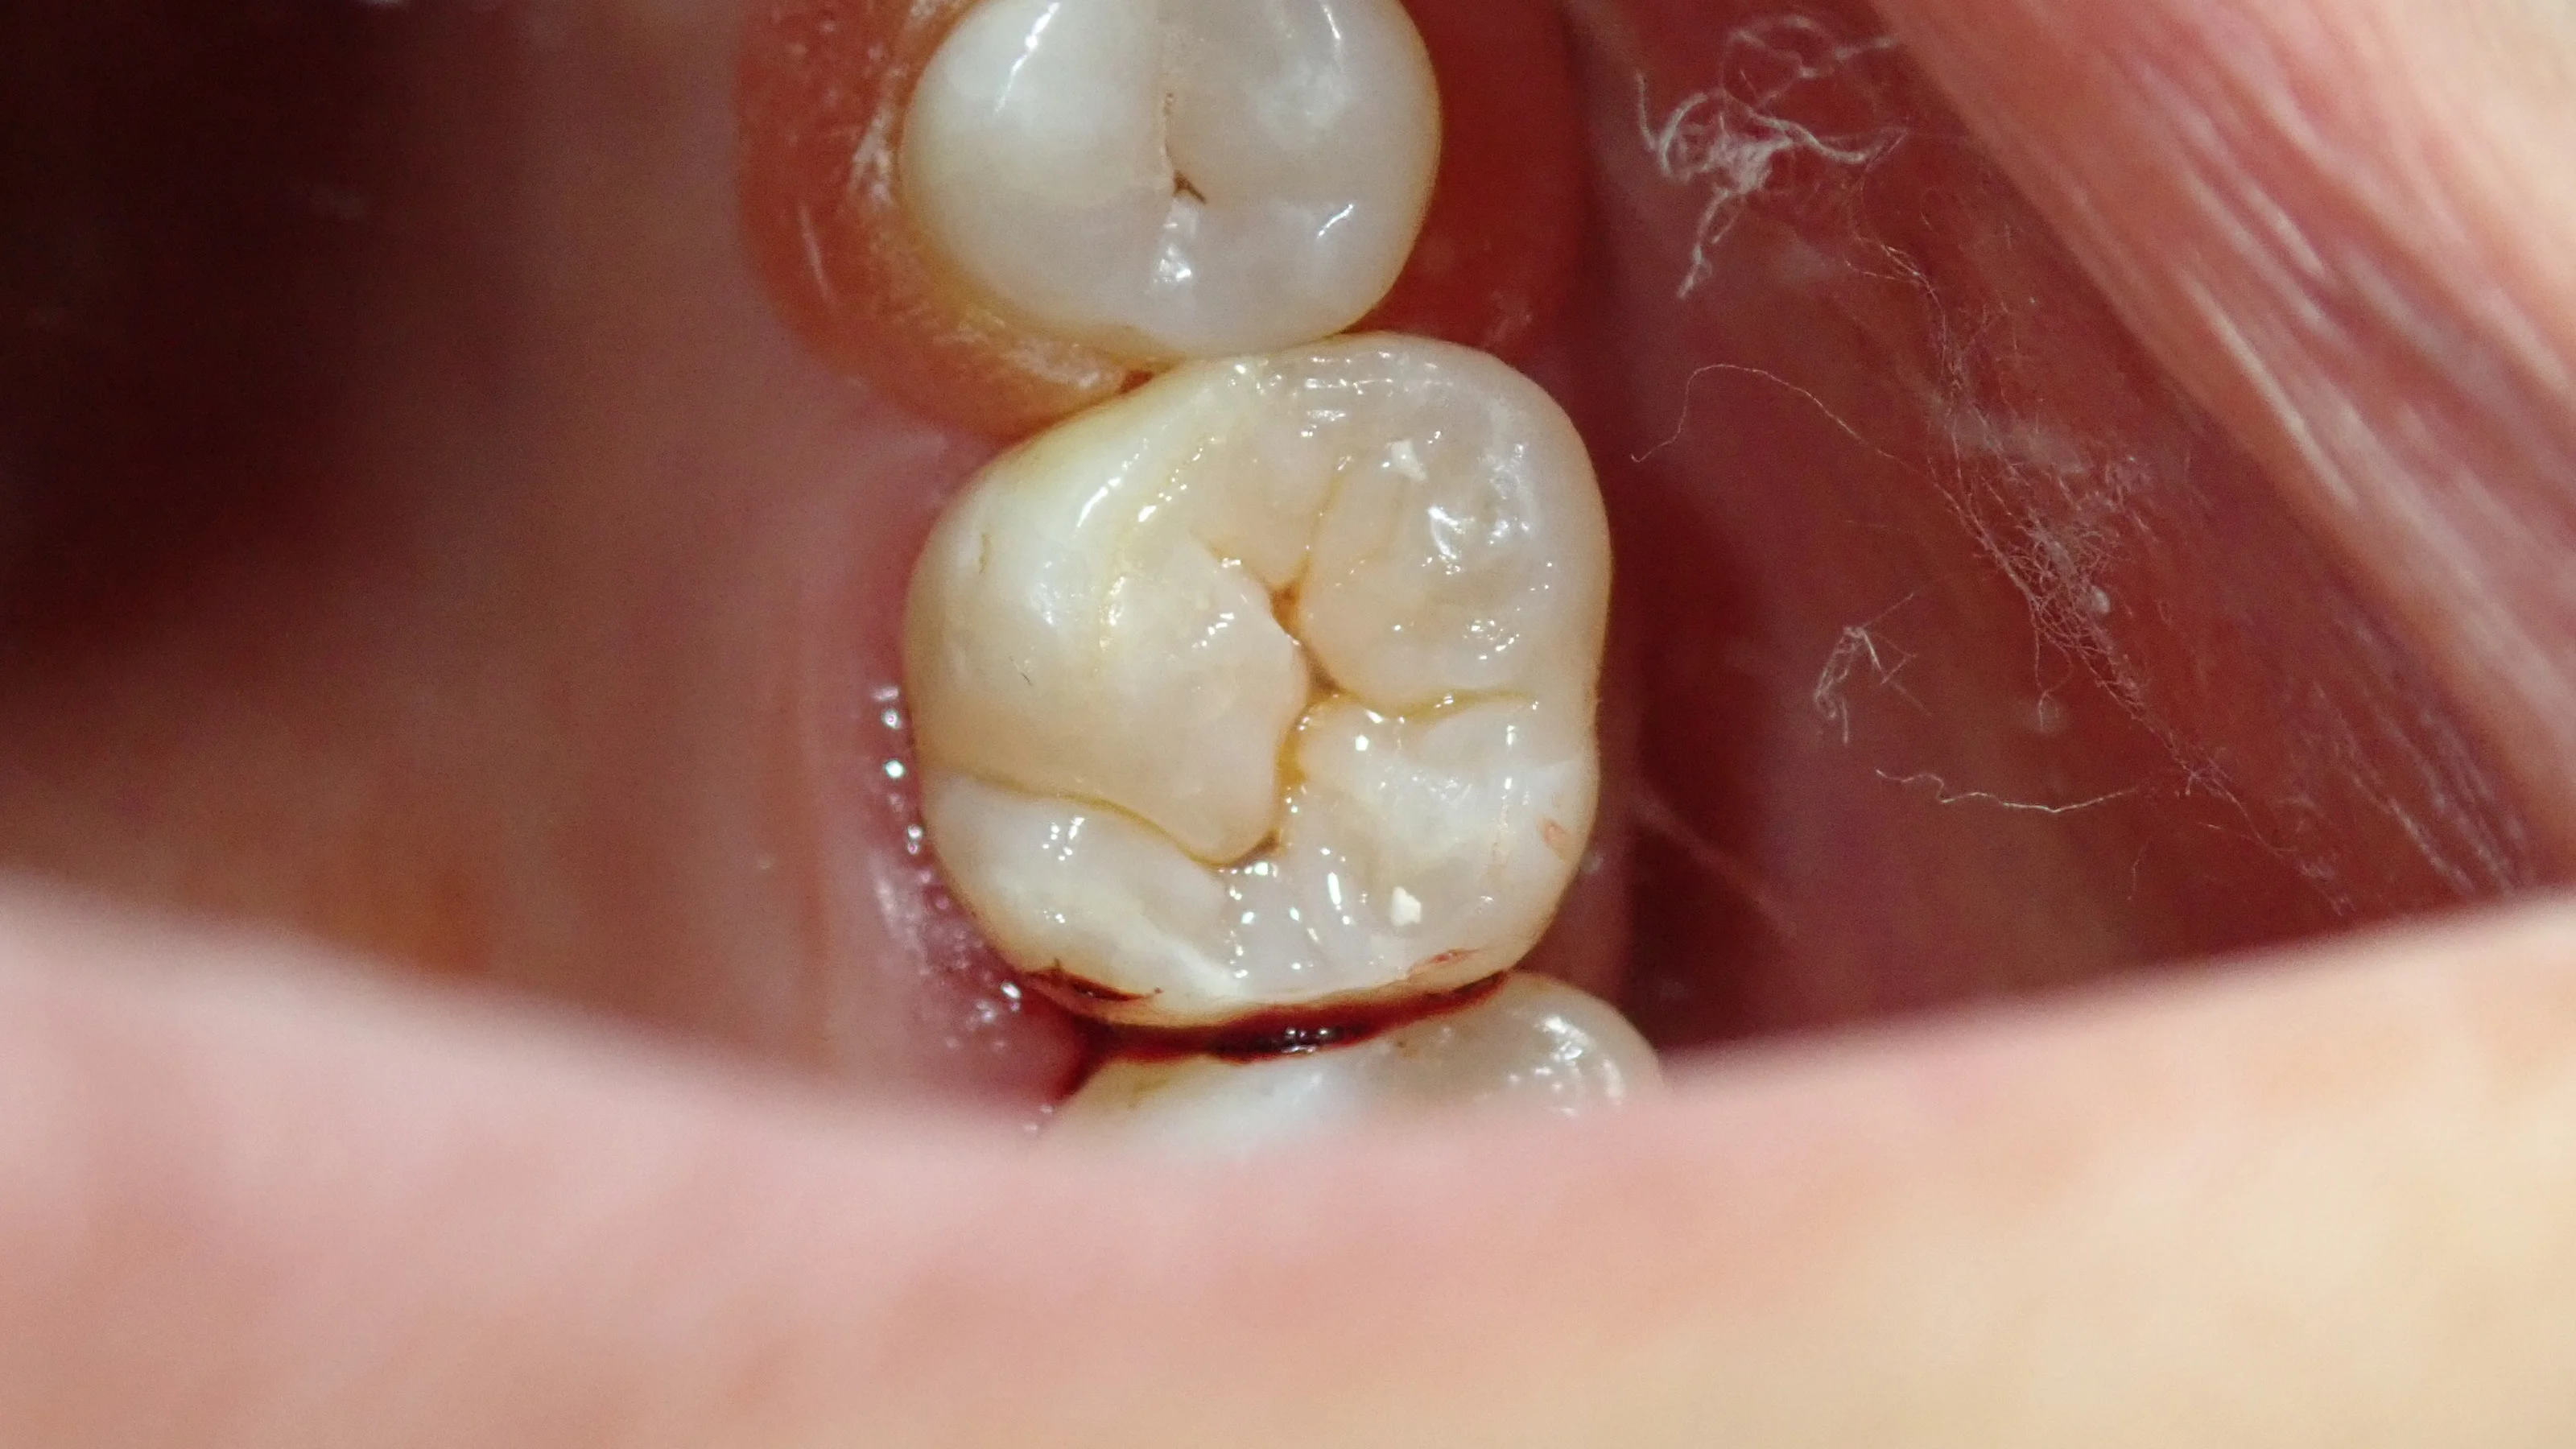

と、いう訳で、噛み合わせの治療後、研磨まで終わった画像がこちらです。

歯を強固に乾燥させていたため、最初に比べると若干色合いが変わってしまっています。

その為、詰めたところが少し浮いているように感じられるかもしれませんが、再度水分を吸ったら1週間くらいで色は馴染んできます。

歯の溝の部分の色を再現することを「ステイニング」と言いますが、これを行うと歯に立体感が出て、より自然な歯に仕上がります。

フロスでも引っかかるところは皆無ですので、十分に長持ちさせることが出来ると思います。

是非、日頃のケアはもちろん、食生活も気を付けていただいて、長持ちさせていただきたいと思います(`・ω・´)!